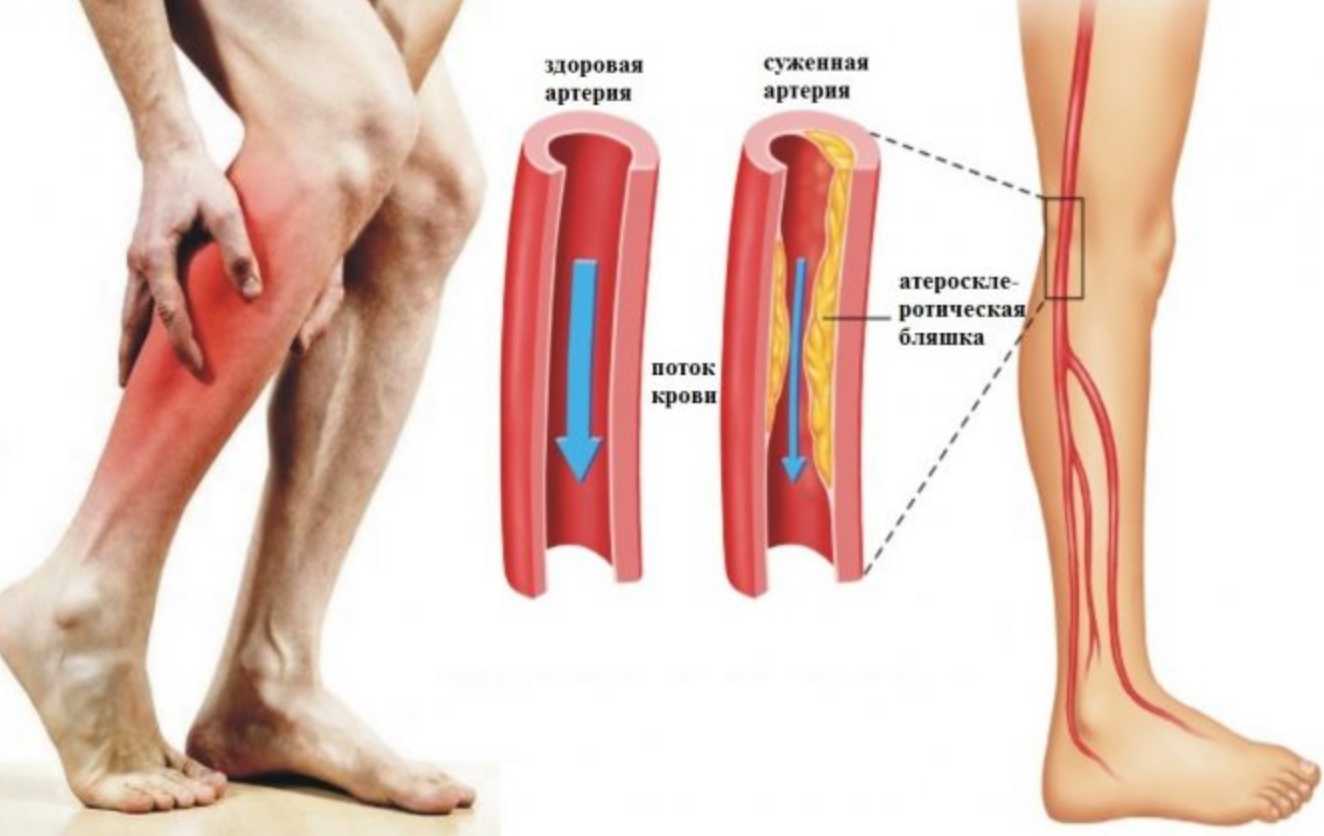

Посетите врача, чтобы исключить серьезные заболевания.